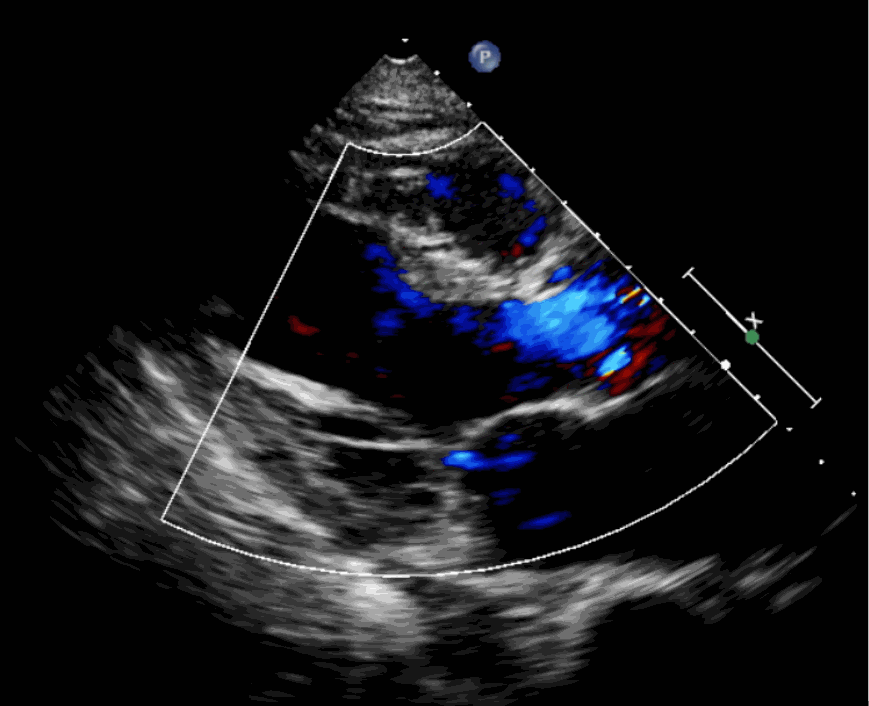

術(shù)前超聲影像圖

該例患者為62歲,女性,因“間歇性心悸、胸悶、氣短、胸痛1年,加重1周”之主訴入院。入院診斷:主動(dòng)脈瓣重度關(guān)閉不全,二尖瓣、三尖瓣輕度關(guān)閉不全,心功能III級(jí);冠狀動(dòng)脈粥樣硬化性心臟病。行心臟超聲心動(dòng)圖提示“主動(dòng)脈瓣重度關(guān)閉不全;瓣口水平以下左室下壁、后下壁搏幅減低;EF值 0.30,左房、左室大、右房大小正常高限;二尖瓣、三尖瓣關(guān)閉不全;輕度肺動(dòng)脈高壓(收縮壓42mmHg);主動(dòng)脈硬化;左室收縮功能重度減低。經(jīng)心血管外科劉洋、楊劍教授、麻醉科陳敏教授及超聲科孟欣教授等專(zhuān)家團(tuán)隊(duì)綜合評(píng)估,判定患者為外科手術(shù)高?;颊?。